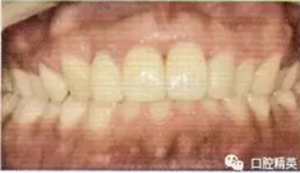

2冠根折,唇側(cè)斷端至齦下2mm,露髓,叩痛(+),不松,齦緣滲血;1冠折,未露髓,部分脫出,叩痛(+),松Ⅲ度,近中齦乳頭撕裂,長約1.5 cm;1挫入,切斷折斷,位于拉冠中部,叩診高調(diào)金屬音,不松,近中齦乳頭撕裂,長約1.5 cm;2見釉質(zhì)裂紋,叩痛(+),不松,齦緣滲血(圖1);以上牙齒X線均未見明顯根折線(圖2)。

圖1外傷即刻口內(nèi)像